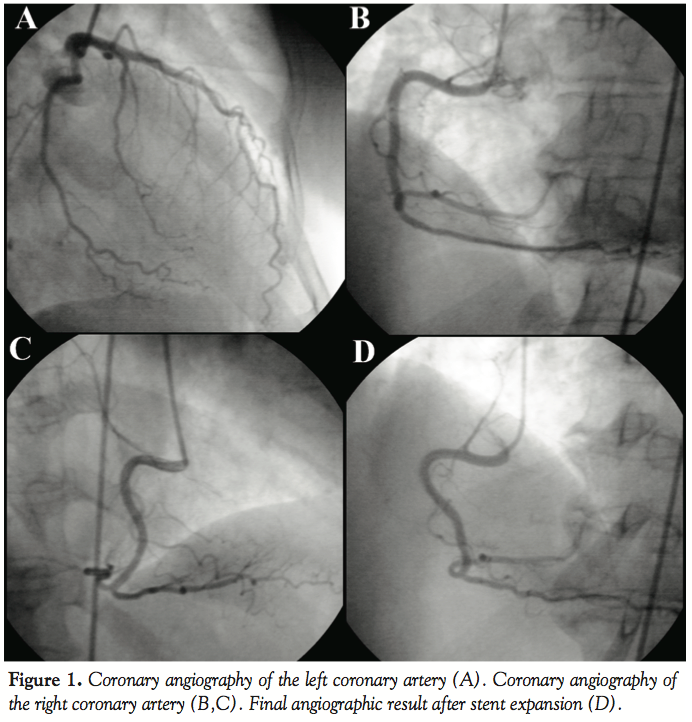

Coronary angiography revealed a normal left coronary artery (Figure 1A). The right coronary artery (RCA) was catheterized using a JR4 6 Fr guiding catheter. However, during attempts to engage the catheter into the ostium of the RCA, significant pressure damping was observed, subsiding with catheter withdrawal. Following a trial contrast injection in the RCA, haziness was temporarily observed in the right posterior lateral branch. Subsequently, the patient was spontaneously restored to sinus rhythm with simultaneous resolution of the ST-segment elevation. Angiography of the RCA did not reveal any obstructive lesions or haziness (Figures 1B and 1C), despite the fact that pressure damping was still present during engagement of the ostium. This raised suspicion of thrombus at the ostium of the vessel. Contrast injection was performed with the catheter resting outside the ostium of the RCA, and a focal contrast deficit was then observed (Figure 2A).

A decision was made to proceed with manual aspiration of the thrombus. A guidewire was inserted into the RCA and manual aspiration with a 10 mm syringe was performed using the guiding catheter, resulting in extraction of small amounts of thrombus. Optical coherence tomography (OCT) was then performed in the proximal 25 mm of the RCA using the C7 LightLab system (LightLab Imaging) and the corresponding intravascular OCT catheter (C7 DragonflyTM). OCT examination revealed the existence of small fragments of thrombus near the ostium of the vessel and the absence of any atheromatic changes of the vascular wall, or any evidence of spontaneous dissection (Figures 2B and 2C). Then, we proceeded with stenting of the RCA ostium using a 4 mm/16 mm Promus stent (Boston Scientific), with a good angiographic result (Figure 1D).